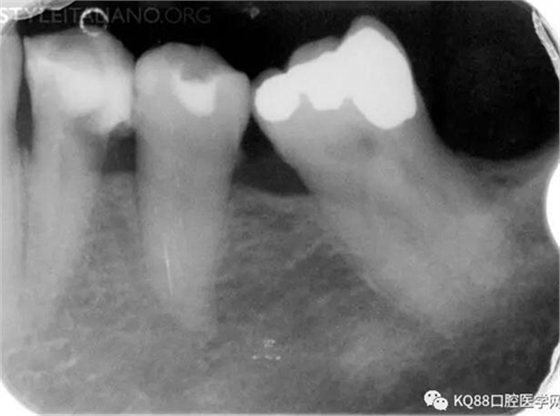

Case 3: This patient was referred for assessment of a first mandibular molar, after an attempted endodontic treatment. Mesio-lingual, mesio-buccal and one distal canal were scouted and filed and a calcium hydroxide temporary dressing was used before referral, but pain persisted. Eventually, most of the temporary obturation material was lost at the time of the visit.

Img. 6 - A careful examination of the pulp chamber floor showed the presence of a middle mesial canal in the mesial root

Img. 7 - And two canals in the distal root

Img. 8 - Endodontic treatment was completed and pain subsided.